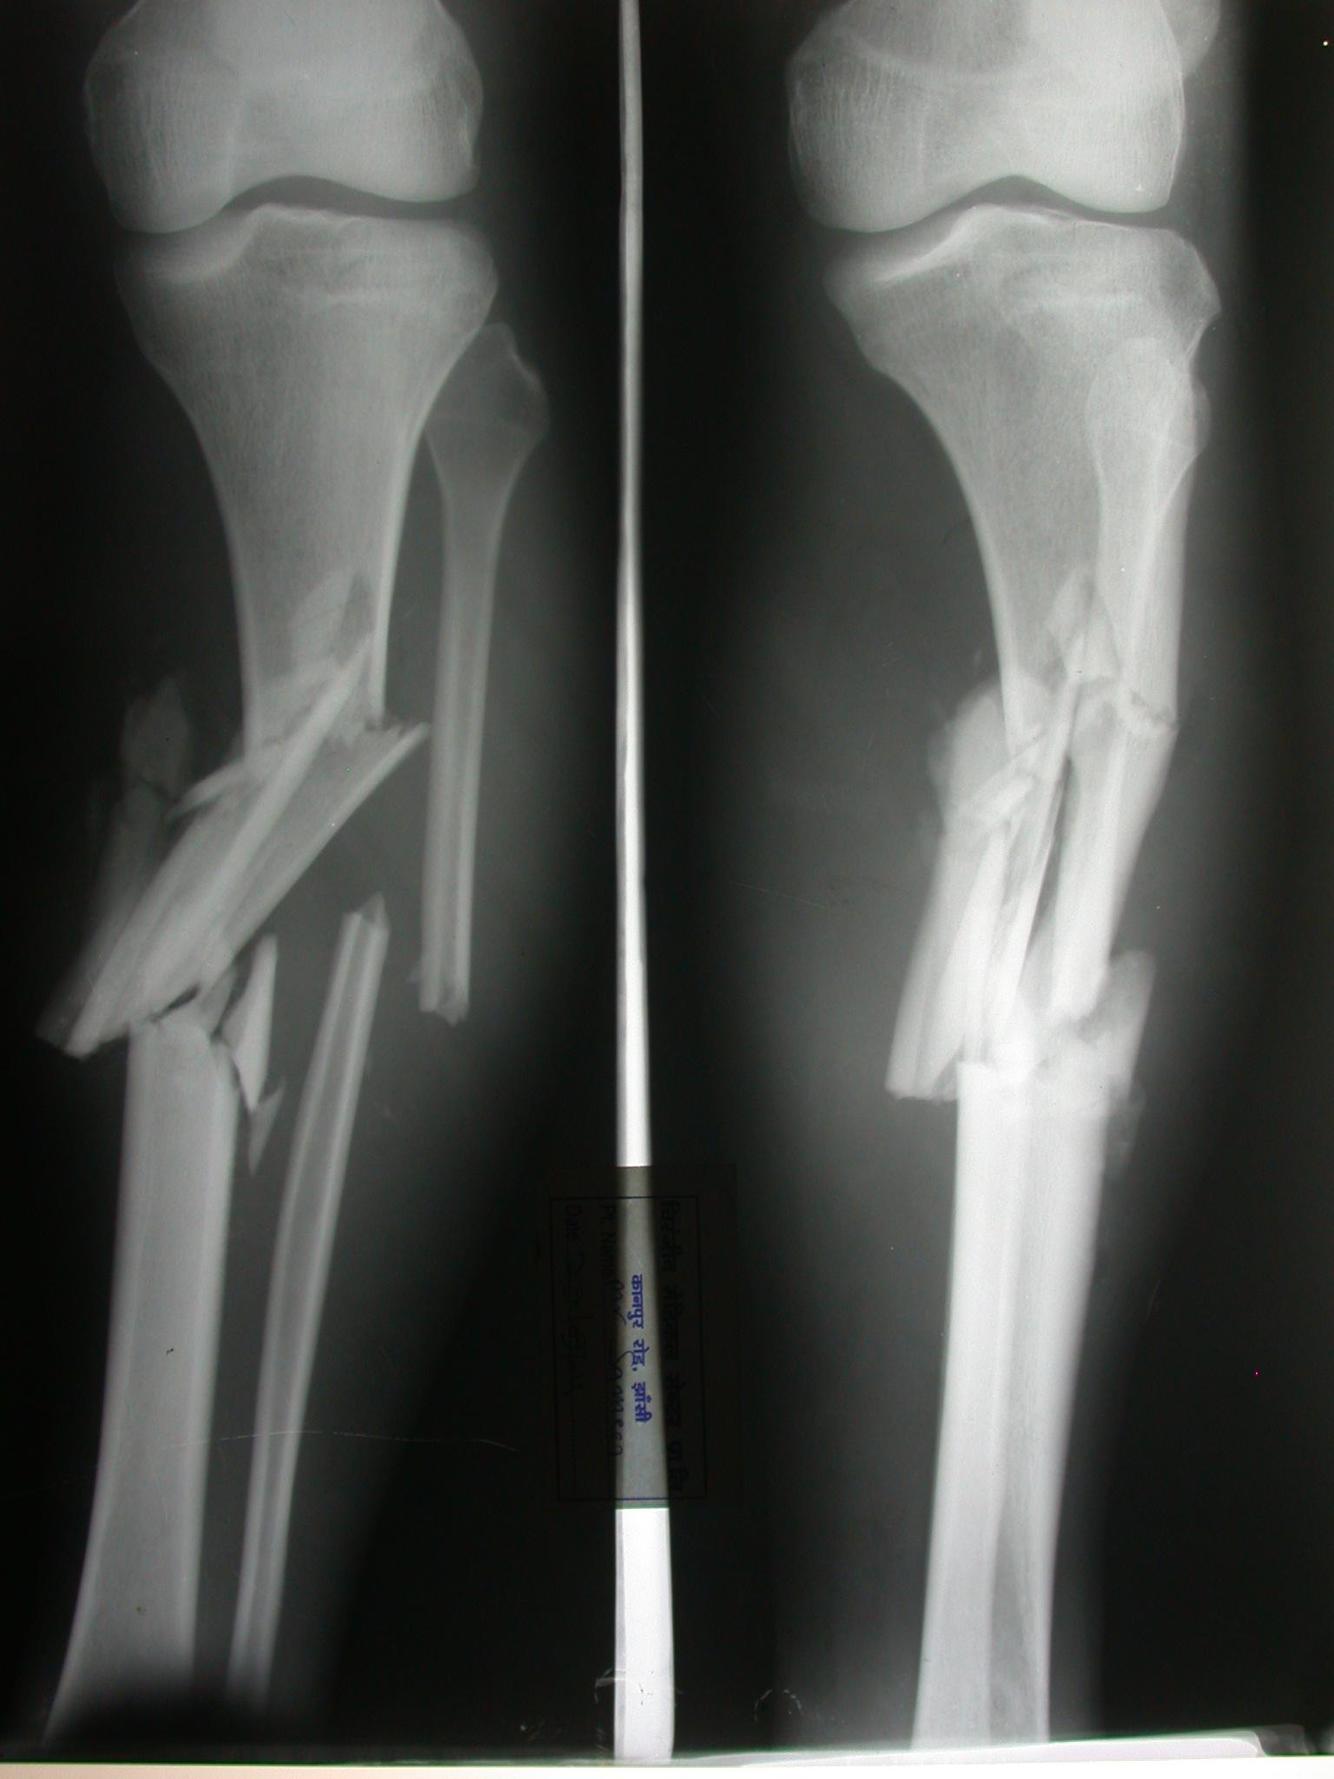

Comminuted fracture